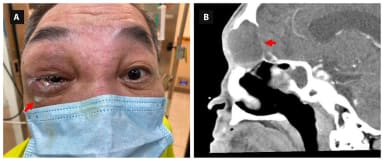

Bei Permanent Make-up speziell am Lid wurden akzidentielle Verletzungen des Auges, z.B. der Hornhaut, beschrieben. Zudem gibt es Auswirkungen auf Anatomie und Funktion der Meibom-Drüsen, die zu einer problematischen Tränenfilminstabilität führen. Die Folge sind vermehrte Oberflächenprobleme der Augen, so das Ergebnis einer aktuellen Studie aus China.3 Verglichen wurden 62 Augen von Frauen mit Lidstrich-Tattoos mit 56 Augen gleichaltriger Frauen ohne eine solche Tätowierung. Folgende Parameter erwiesen sich als signifikant schlechter: